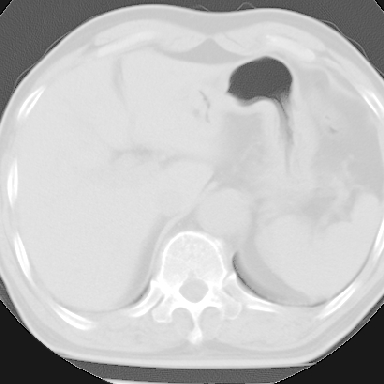

标题: CT8275:M 77 反复咳嗽咳痰10多年,慢性支气管炎请分析 [打印本页]

标题: CT8275:M 77 反复咳嗽咳痰10多年,慢性支气管炎请分析

m 77 反复咳嗽咳痰10多年,再发加重4天

两肺未见明显异常;主动脉弓硬化;左侧冠状动脉硬化?